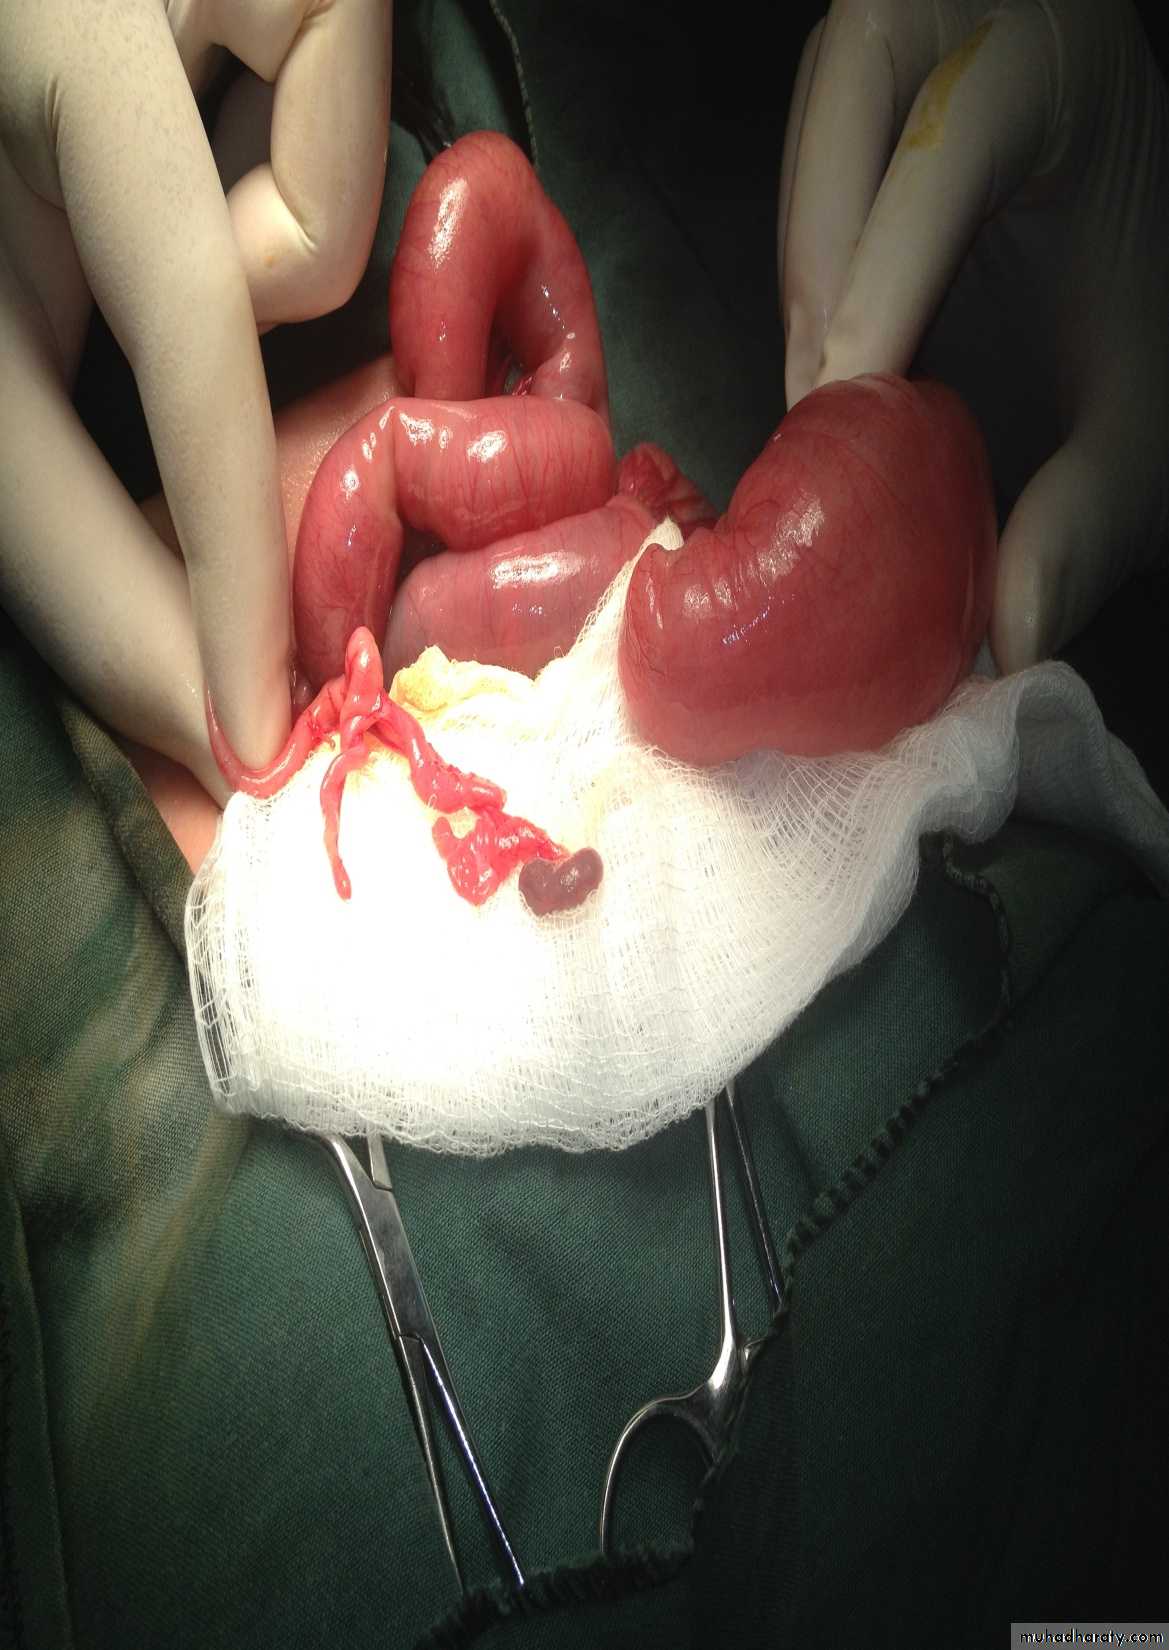

Subcostal incision

content

Defect=sac